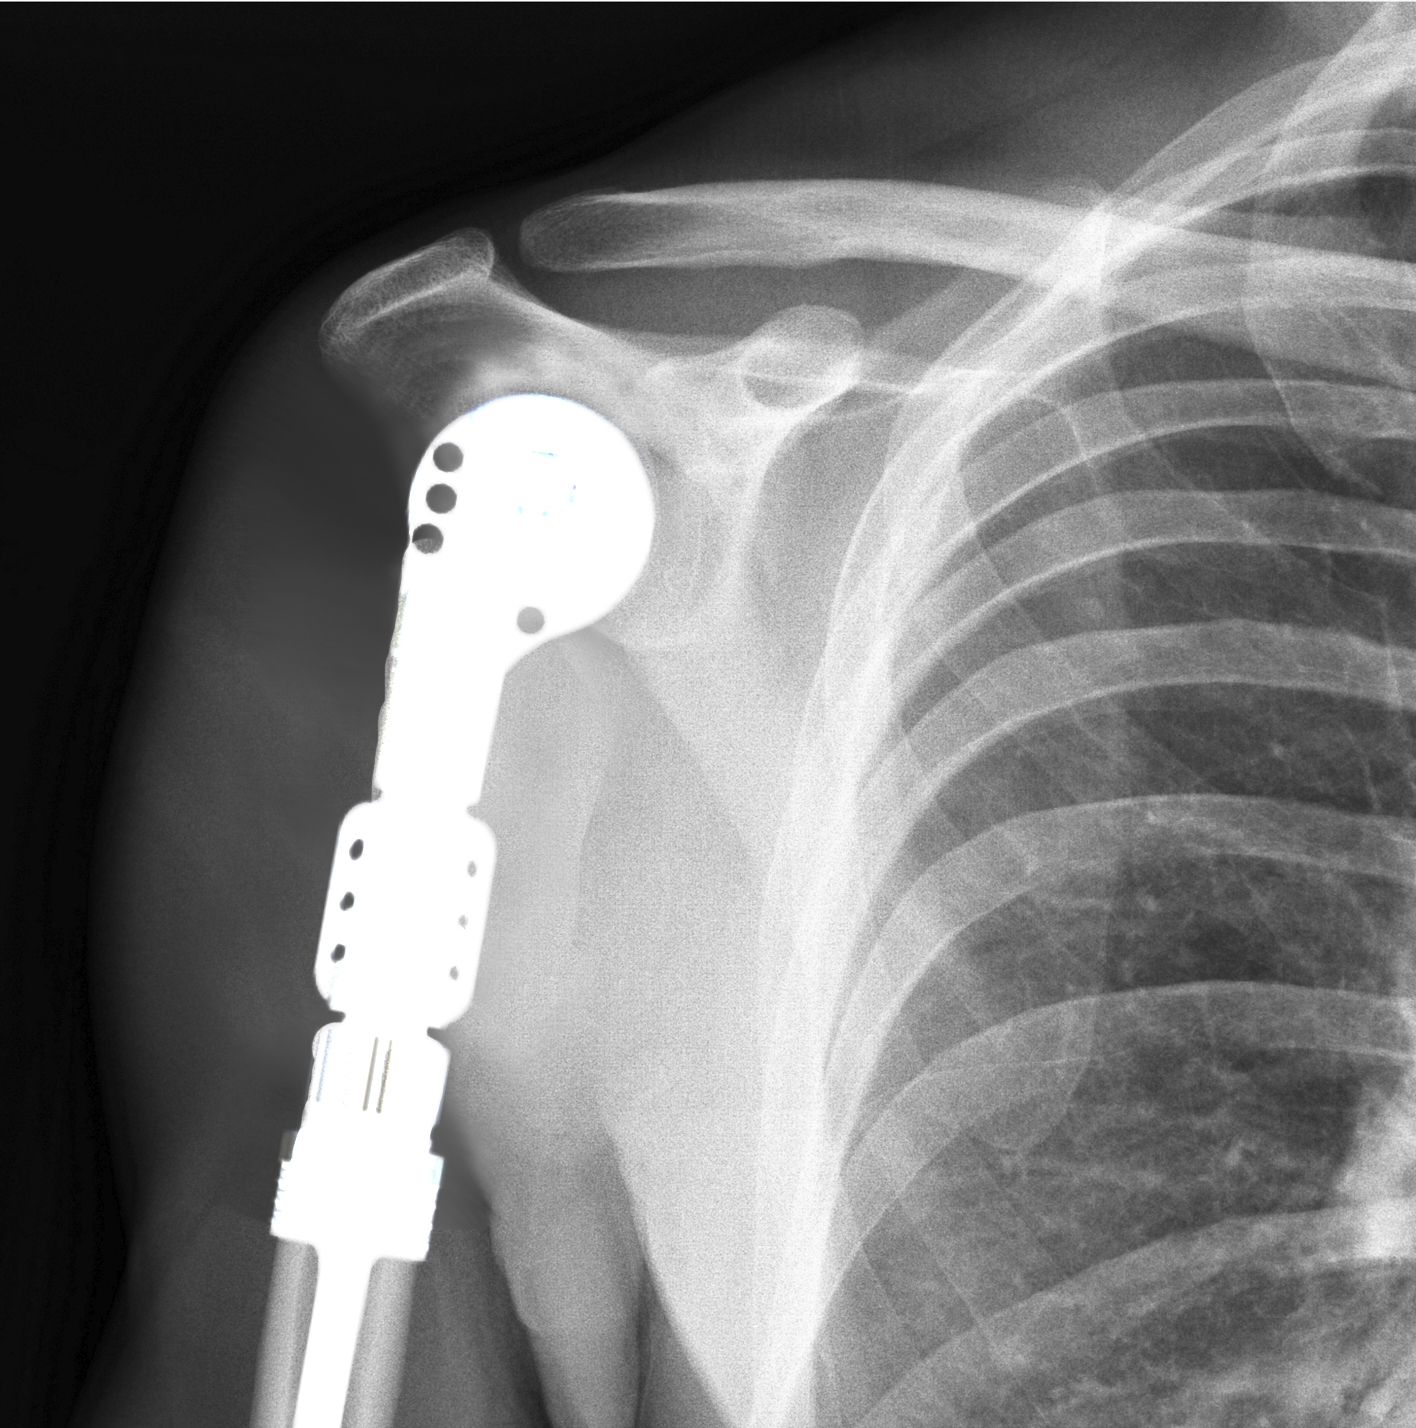

Revision Shoulder Replacement

Total shoulder replacement usually has good results, but a revision surgery may occasionally be necessary due to persistent pain, infection, stiffness, weakness, instability, hardware loosening, malposition or fracture.

Revision Shoulder Arthroplasty

Shoulder arthroplasty, or shoulder replacement surgery, is a surgical procedure to replace the damaged parts of the shoulder joint with artificial components.